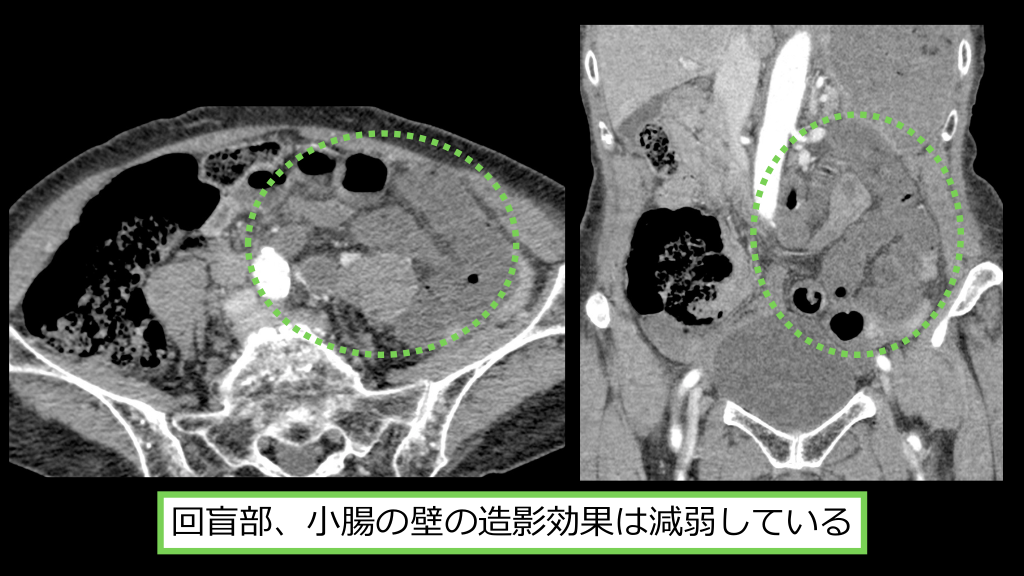

回盲部、⼩腸の壁の造影効果は減弱している